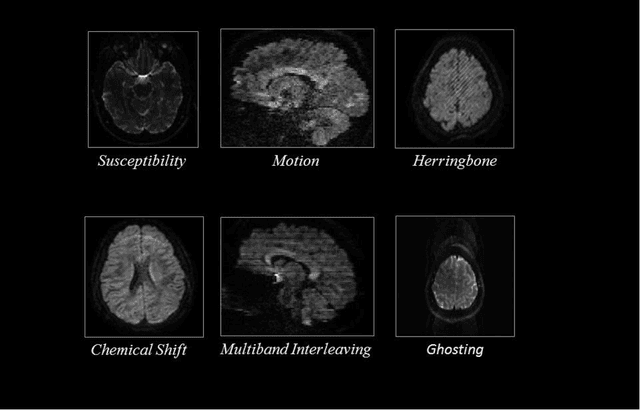

Quality assessment of diffusion MRI (dMRI) data is essential prior to any analysis, so that appropriate pre-processing can be used to improve data quality and ensure that the presence of MRI artifacts do not affect the results of subsequent image analysis. Manual quality assessment of the data is subjective, possibly error-prone, and infeasible, especially considering the growing number of consortium-like studies, underlining the need for automation of the process. In this paper, we have developed a deep-learning-based automated quality control (QC) tool, QC-Automator, for dMRI data, that can handle a variety of artifacts such as motion, multiband interleaving, ghosting, susceptibility, herringbone and chemical shifts. QC-Automator uses convolutional neural networks along with transfer learning to train the automated artifact detection on a labeled dataset of ~332000 slices of dMRI data, from 155 unique subjects and 5 scanners with different dMRI acquisitions, achieving a 98% accuracy in detecting artifacts. The method is fast and paves the way for efficient and effective artifact detection in large datasets. It is also demonstrated to be replicable on other datasets with different acquisition parameters.